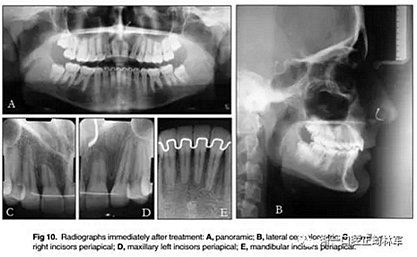

最終的X線評估(圖10)表現(xiàn)出良好的根并行性。上頜中切牙有嚴重的牙根吸收。然而,臨床上這些牙齒的牙周穩(wěn)定性良好。頭影測量分析顯示上頜骨和下頜骨門牙的傾斜度和位置良好。在治療期間觀察到幾乎沒有骨骼改變。